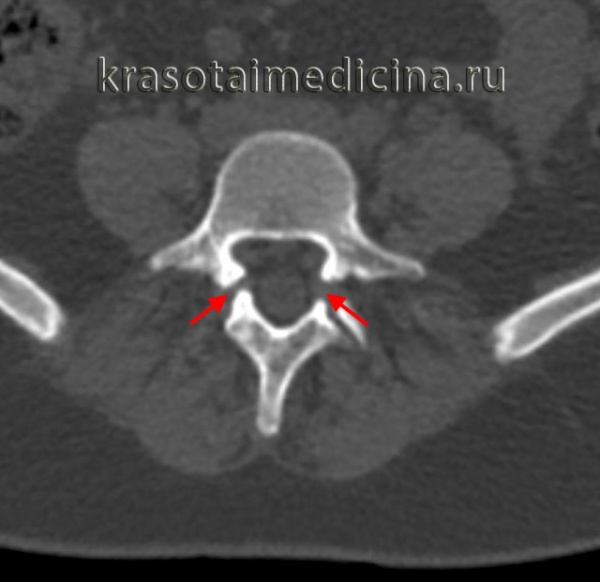

о Симптом «незавершенного кольца» на аксиальных изображениях:

- Нарушение непрерывности кольца, образованного телом и дугой позвонка

о Зона дефекта может выглядеть как дугоотростчатый сустав:

- Признаки «добавочной фасетки»

- Горизонтальная или косая ориентация

- Неправильной формы или ровные кортикальные края

КТ пояснично-крестцового отдела позвоночника. Нарушение целостности задних отделов позвонка без существенного спондилолистеза.